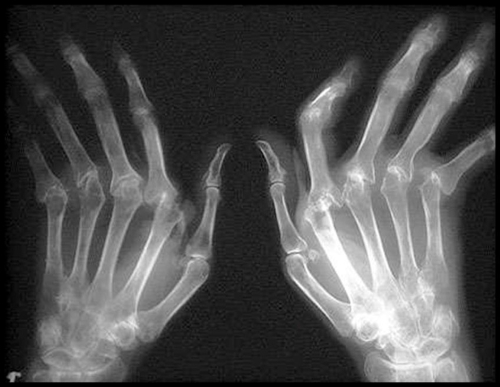

Рентгенография — важный диагностический инструмент для выявления заболеваний. Существуют несколько рентгенологических признаков, характерных для различных форм олигоартрита:

- Гнойная форма болезни проявляется околосуставным остеопорозом и уменьшением ширины суставной щели.

- Хронический олигоартрит без нагноения характеризуется образованием краевых кист и эрозий, возникающих после остеопороза и сужения суставной щели.

- Олигоартрит, затрагивающий периферические суставы, сопровождается пролиферацией тканей вокруг эрозий и в местах прикрепления сухожилий, а также периоститом.

- Псориатическая форма болезни проявляется специфическими разрушениями дистальных суставов, костными подвывихами и остеолизом.

- Подагрическая форма характеризуется изменениями в суставах больших пальцев ног, краевыми эрозиями и внутрисуставными кистами.